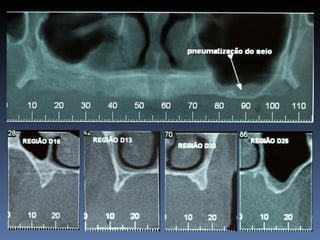

BOX 5 Rui FreitasGomes Idade – 64 anos Sexo – Masculino Raça – Caucasiana ASA – II Data- 26-04-2012 Diagnóstico: Atrofia vertical maxilar posterior. Plano de tratamento: “Sinus-lift” bilateral , com aloenxerto ósseo proveniente de diáfise de Tíbia - Fresco-congelado, para instalação de implantes endo-ósseos, e reabilitação protética fixa.

Diagnóstico: Atrofia vertical

maxilar posterior.

Plano de tratamento: “Sinus-lift” bilateral , com

aloenxerto ósseo proveniente de diáfise de Tíbia -

Fresco-congelado,       para instalação de implantes

endo-ósseos, e reabilitação protética fixa.